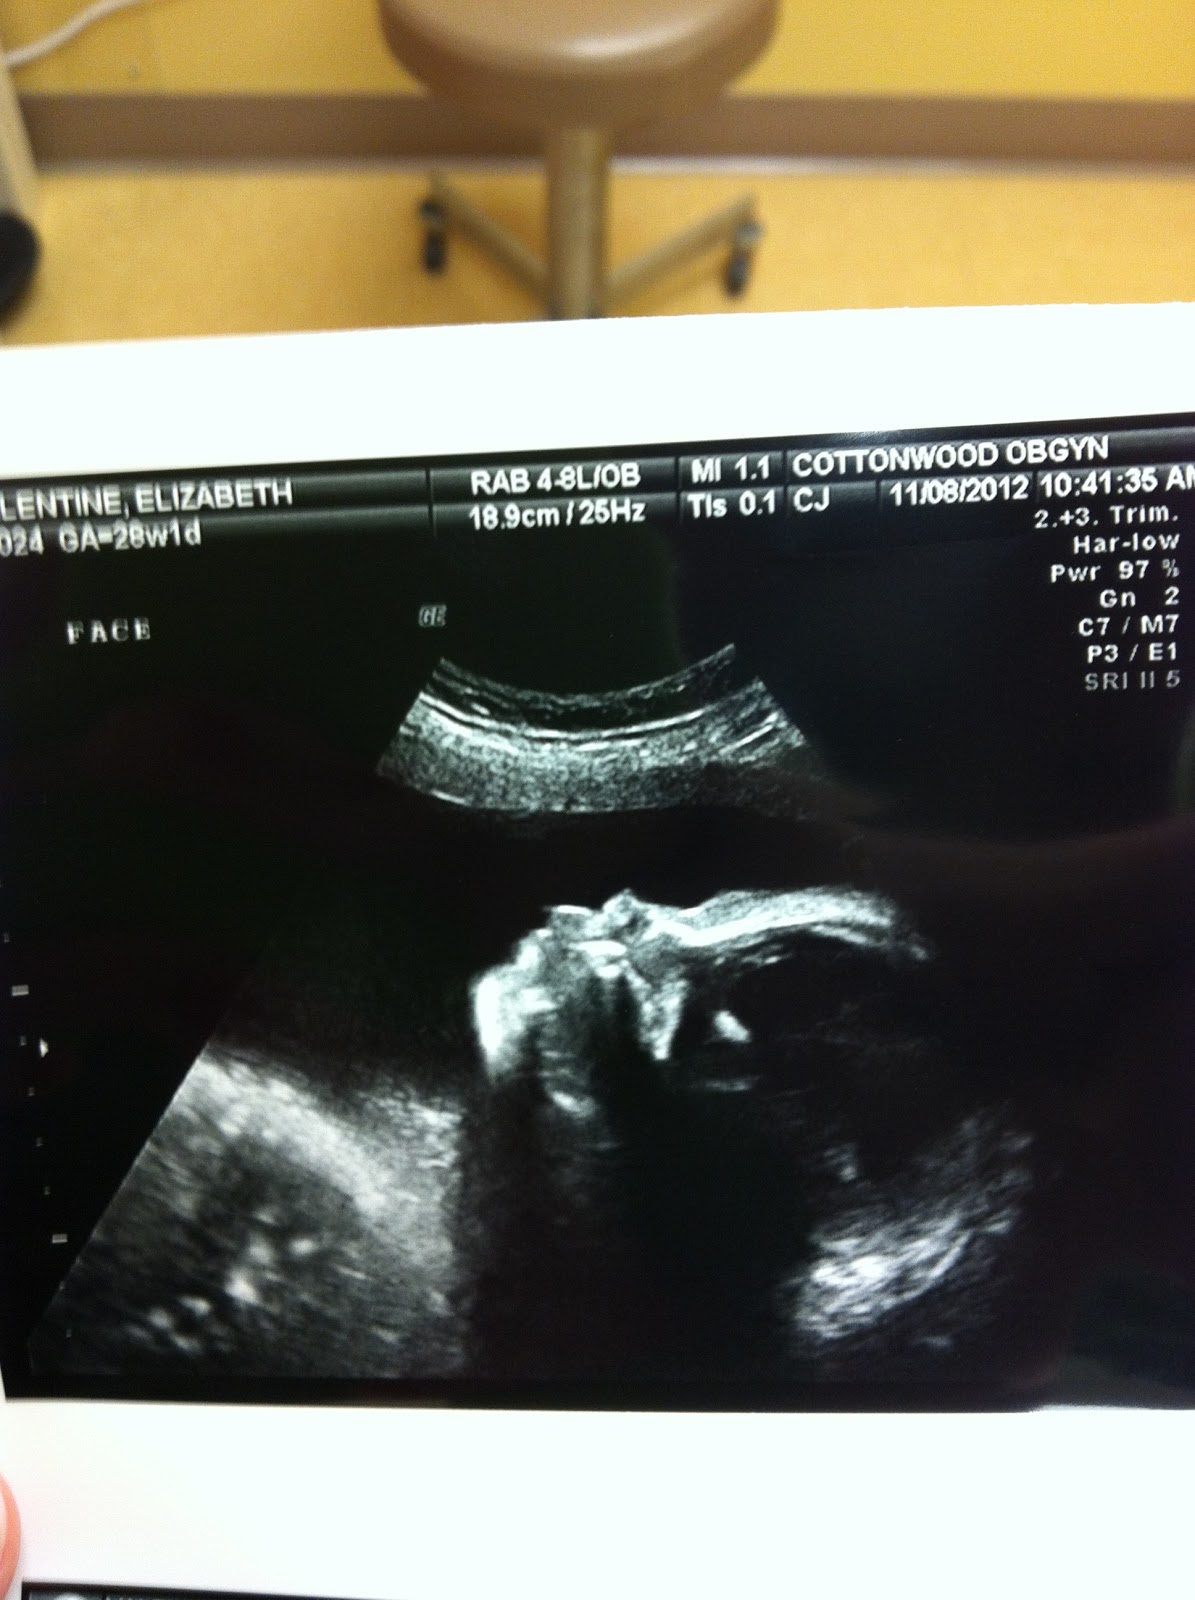

Soon after that, James and I dropped Olivia off with friends and went to a long morning at the OBGYN office. We had another ultrasound to see if our little boy is going to have clubbed feet. While we need to wait for the radiologist to assess the pictures, no one could help but notice how nice and straight his legs to his feet were. I am hopeful. Then we got to stick around for an appointment and the gestational diabetes test (that drink is foul).

We got some fun views of our baby boy!

Grandma was kind enough though to point out that his profile looks like Darth Vader.